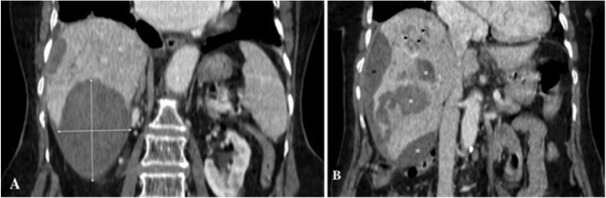

出血是一种非常罕见的法氏囊属(F. hepatica 或 F. gigantica)感染并发症。我们在此报告了土耳其东南部迪亚巴克尔省的三例由肝期法氏囊属感染引起的肝囊下出血病例,其中两例为女性,年龄分别为22岁、66岁和84岁。他们的症状包括右上腹疼痛(3 例)、恶心(1 例)和呕吐(2 例),持续时间从 6 小时到 15 天不等。所有患者的临床表现从中度腹痛到低血容量性休克和缺血性肝炎,均在支持性治疗后得到改善,无需手术。他们在服用曲克芦苯咪唑后,临床和化验指标均完全恢复。总之,肝病出血的病因应考虑法氏囊属感染。

Bleeding is a very rare complication of Fasciola species (F. hepatica or F. gigantica) infection. We present here three cases of subcapsular liver bleeding caused by the hepatic phase of Fasciola spp. infection in patients, two of whom were women, aged 22, 66, and 84 years in Diyarbakir Province, southeastern Turkey. They had symptoms of right upper quadrant pain (n = 3), nausea (n = 1), and vomiting (n = 2) for periods ranging from 6 hours to 15 days. All patients with clinical presentations ranging from moderate abdominal pain to hypovolemic shock and ischemic hepatitis were improved with supportive treatment without the need for surgery. They showed complete clinical and laboratory recovery after triclabendazole administration in their follow-up. In conclusion, Fasciola spp. infection should be considered in the etiology of bleeding from liver disease.